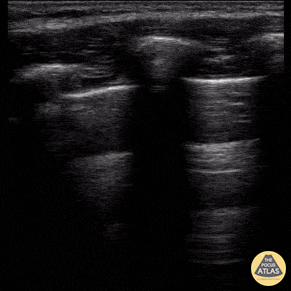

Peds-Lung - Normal Lung Sliding During FAST Exam

11 year old female presented to the emergency department with a puncture wound to her left chest wall. FAST exam did not reveal any intraabdominal free fluid, and there was lung sliding bilaterally, suggesting no pneumothorax. The patient had her wound explored, repaired, and was discharged home. Contributed by: Zach Boivin, MD, @ZachBoivinMD